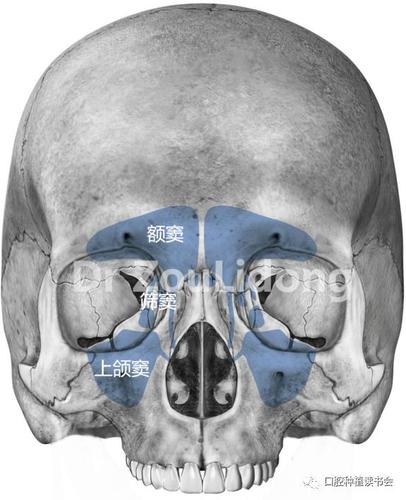

上颌窦5个壁图片,上颌窦解剖图

成人上颌窦大致呈朝向外侧的锥形,平均3.75 cm(高)× 2.

上颌窦壁

上颌窦5个壁

上颌窦几个壁